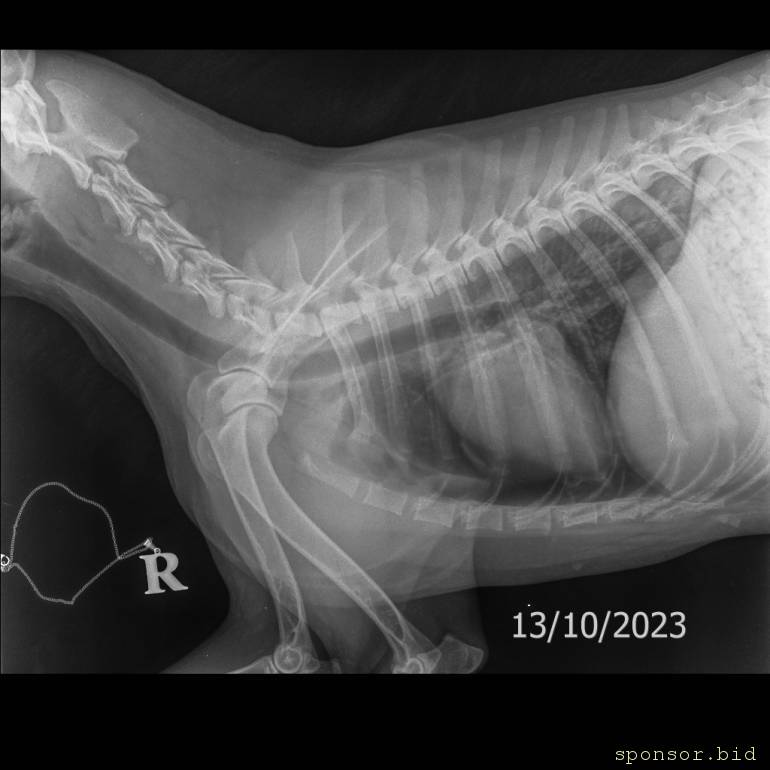

На втором снимке видно как раздроблена кость

Мою собаку сбила машина - Мягкие ткани Средний 10-25 kg -Брюшная полость LAT-13.10.2023-15_31_40-951.JPEG